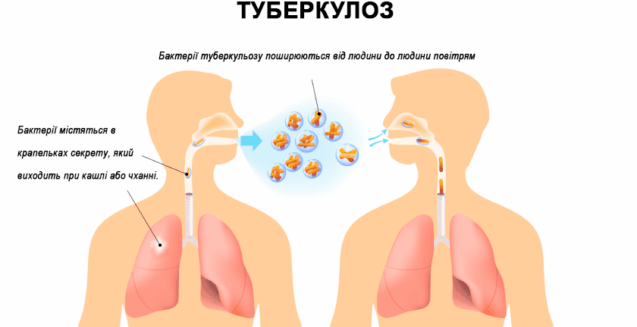

Туберкульоз – це інфекційне захворювання, збудником якого є мікобактерія туберкульозу, котра передається переважно повітряно-крапельним шляхом від хворої людини до здорової. Туберкульоз, у більшості випадків, уражає легені, але захворювання може ушкодити будь-який орган, наприклад: нирки, хребет, мозок, лімфатичні вузли, кишечник, шкірні покриви, статеві органи тощо.

Туберкульозом можна заразитися при вдиханні повітря, в якому є мікобактерія туберкульозу, яку ще називають паличкою Коха, на честь науковця, що відкрив цей збудник у 1882 році. Цей мікроорганізм не схожий на інші мікроби. Його унікальність, насамперед, полягає у тому, що він є стійким до умов навколишнього середовища